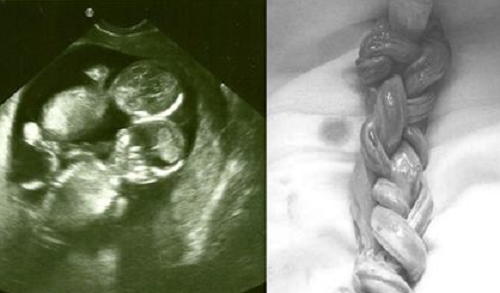

Dù dây rốn quấn chặt như tết tóc vào nhau và thai nhi bị mắc hội chứng Monoamniotic nhưng khi mổ đẻ cho ca song sinh, các bác sĩ đã sốc khi phát hiện 2 em bé vẫn sống sót